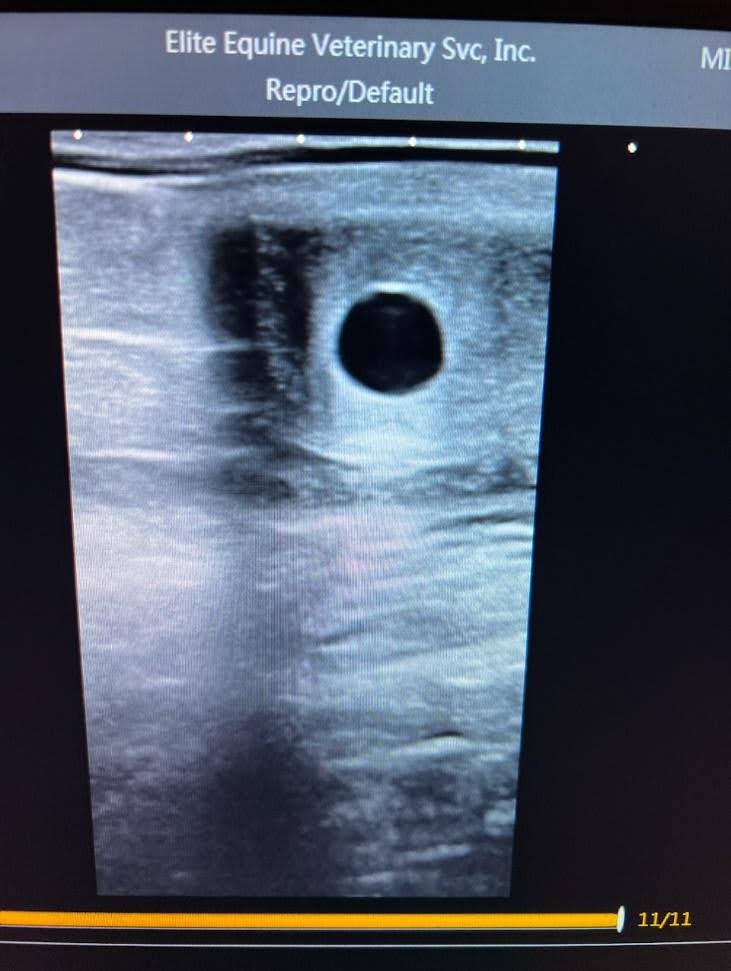

We did another ultrasound which showed a big, healthy foal!